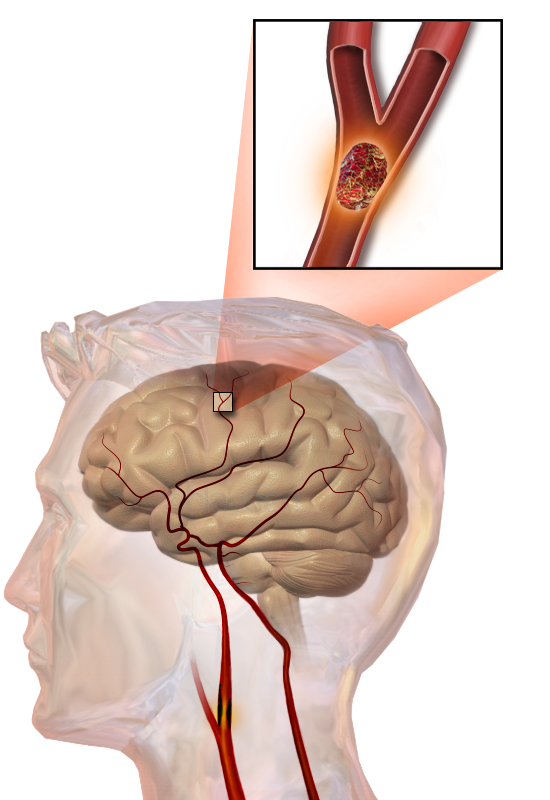

뇌경색이란

무엇인가 뇌경색은 뇌혈관이 혈전이나 지방 침착 등으로 막혀 뇌에 혈액 공급이 중단되는 상태를 말합니다.

뇌세포는 산소 공급이 끊기면 몇 분 내에 손상되기 시작하므로, 신속한 치료가 필수적입니다.